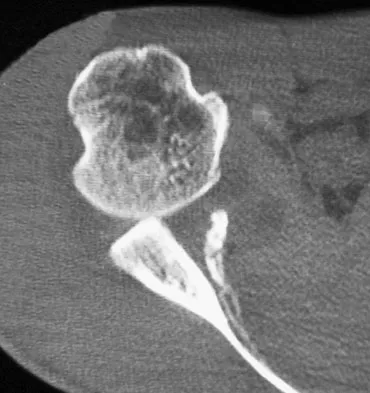

Which of the following findings best describes the acetabular fracture shown in Figure 38?

Explanation

The CT scan shows a posterior wall fracture with impaction of the articular surface and a free fragment within the joint. Proper treatment of this injury requires not only reduction and fixation of the posterior wall fragment but also removal of the free fragment and elevation of the depressed articular segment. Letournel E, Judet R: Fractures of the Acetabulum, ed 2. Berlin, Germany, Springer Verlag, 1993.